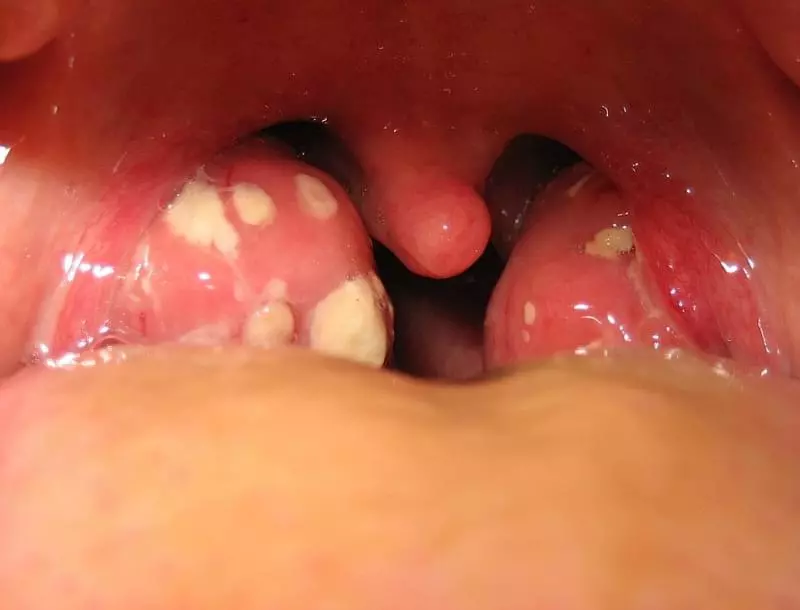

Багато людей стикаються з проблемою появи нальоту на гландах. Цей білий або жовтуватий шар може викликати дискомфорт, біль у горлі і навіть неприємний запах з рота. Отже, чим зняти наліт на гландах? Розгляньмо різноманітні методи, які допоможуть вам позбутися цієї неприємності.

- Інфекції. Вірусні чи бактеріальні інфекції, такі як ангіна або фарингіт, часто є винуватцями.